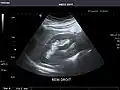

Liver

Ultrasonography of the liver with some standard measurements[6]

In patients with deranged liver function tests, ultrasound may show increased liver size (hepatomegaly), increased reflectiveness (which might, for example, indicate cholestasis), gallbladder or bile duct diseases, or a tumor in the liver.

Ultrasonography of liver tumors involves two stages: detection and characterization. Tumor detection is based on the performance of the method and should include morphometric information (three axes dimensions, volume) and topographic information (number, location specifying liver segment and lobe/lobes). The specification of these data is important for staging liver tumors and prognosis. Tumor characterization is a complex process based on a sum of criteria leading towards tumor nature definition. Often, other diagnostic procedures, especially interventional ones, are no longer necessary. Tumor characterization using the ultrasound method will be based on the following elements: consistency (solid, liquid, mixed), echogenicity, structure appearance (homogeneous or heterogeneous), delineation from adjacent liver parenchyma (capsular, imprecise), elasticity, posterior acoustic enhancement effect, the relation with neighboring organs or structures (displacement, invasion), vasculature (presence and characteristics on Doppler ultrasonography and contrast-enhanced ultrasound (CEUS).